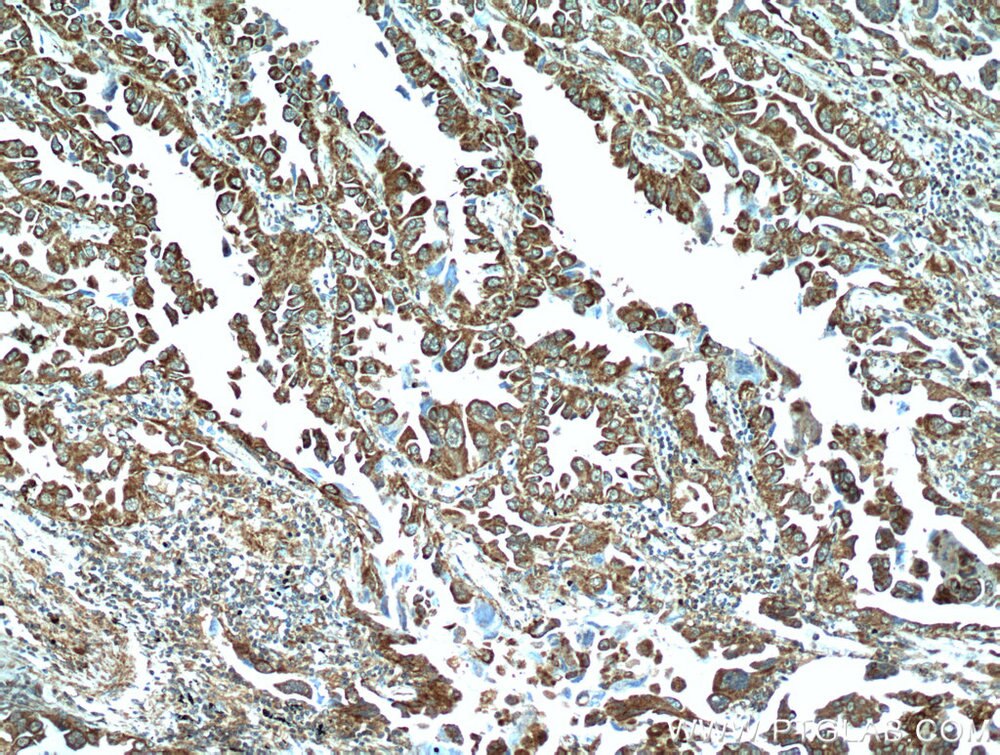

| Positive IHC detected in | human lung cancer tissue Note: suggested antigen retrieval with TE buffer pH 9.0; (*) Alternatively, antigen retrieval may be performed with citrate buffer pH 6.0 |

| Immunohistochemistry (IHC) | IHC : 1:20-1:200 |